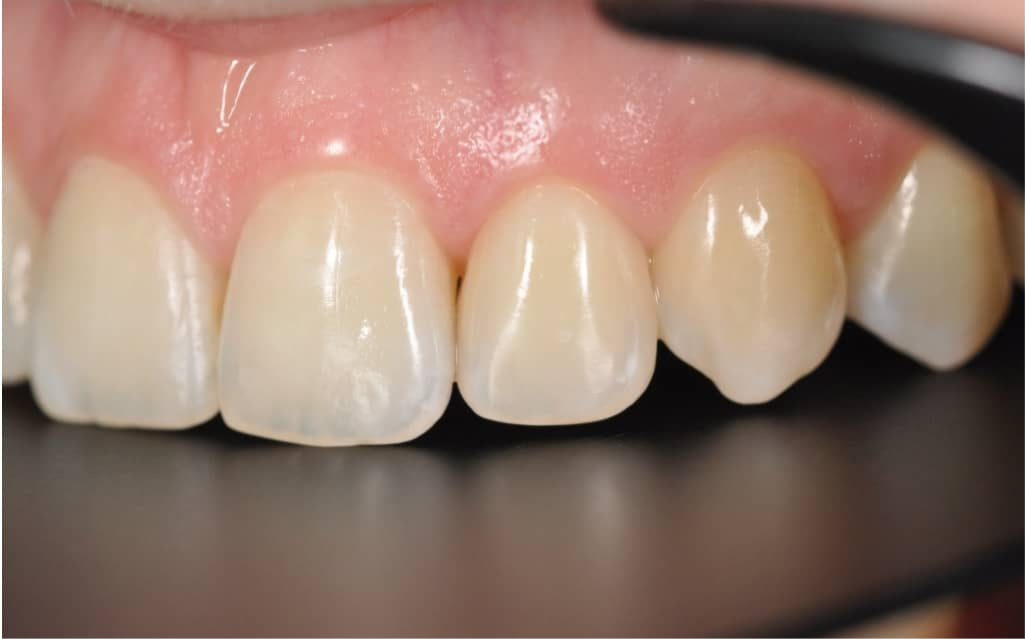

Этап №4

Финишная реставрация

После снятия брекет-системы стоматолог-терапевт провела художественную реставрацию формы боковых резцов, добившись идеальной гармонии и естественности улыбки.

Эстетика

Исправлен прямой прикус, восстановлена форма резцов, а улыбка стала не только красивой, но и здоровой с точки зрения биомеханики.